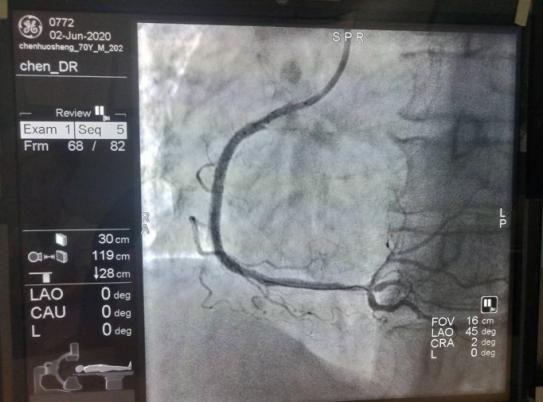

5月26日21时,一名70岁的男性患者,因突发胸痛3小时以“胸痛原因待查”,心电图提示:窦性心律,V1-V5导联ST段上斜型抬高,入科后立即予心电监护,监测生命体征。凌晨1点30分接危急值提示:肌钙蛋白I:1 .12ng/ml,患者既往有前降支和回旋支各植入一枚支架,右冠植入两枚支架病史。陈洪主任结合患者病情决定行冠状动脉造影术,经患者和家属同意后,5月29日在陈洪主任及余波主治医生为行冠状动脉造影术,术中顺利,造影结果提示:右冠中段原支架内狭窄80%。陈洪主任看到造影结果后,建议在右冠支架内病变处行药物球囊扩张术,经患者和家属同意后,于6月2日行药物球囊扩张术,术中快速将药物球囊放入到血管狭窄处,高压将药物球囊扩张,保留1分钟,药物释放后充分涂匀在血管壁上防止再次狭窄,术中顺利,术后效果良好,避免了患者再次放入支架的风险。